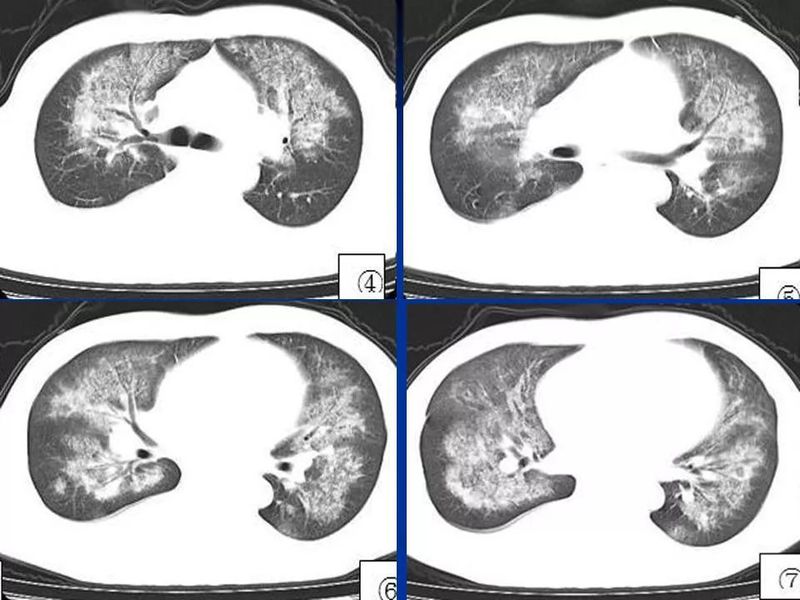

主任提醒:这个病很容易误诊为肺炎!